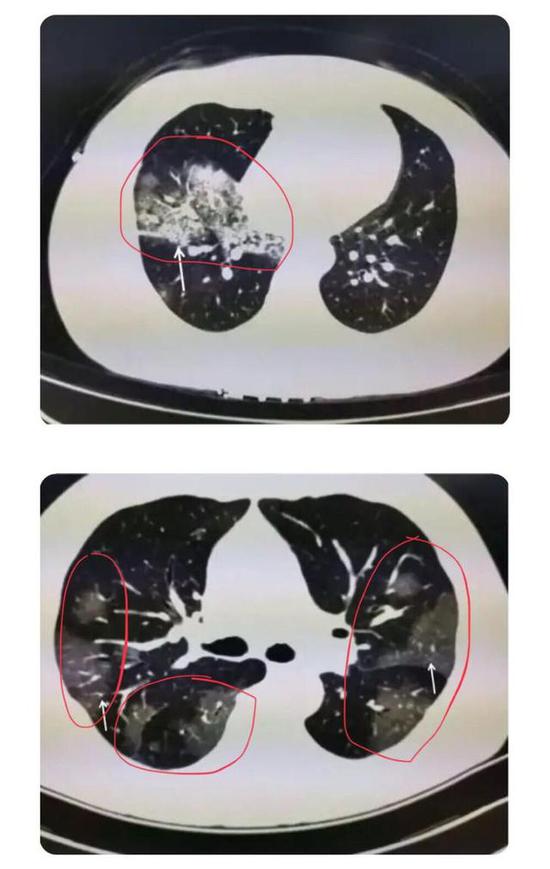

根据感染程度不同,有的仅单侧肺出现这种磨玻璃影,还有的双侧都有。磨玻璃影可以累及一个肺叶,也可同时累及多个肺叶。

▲上面的图:单侧肺出现磨玻璃影,累及一个肺叶; ▲下面的图:双侧肺均出现磨玻璃影,累及多个肺叶(图片来自网络)